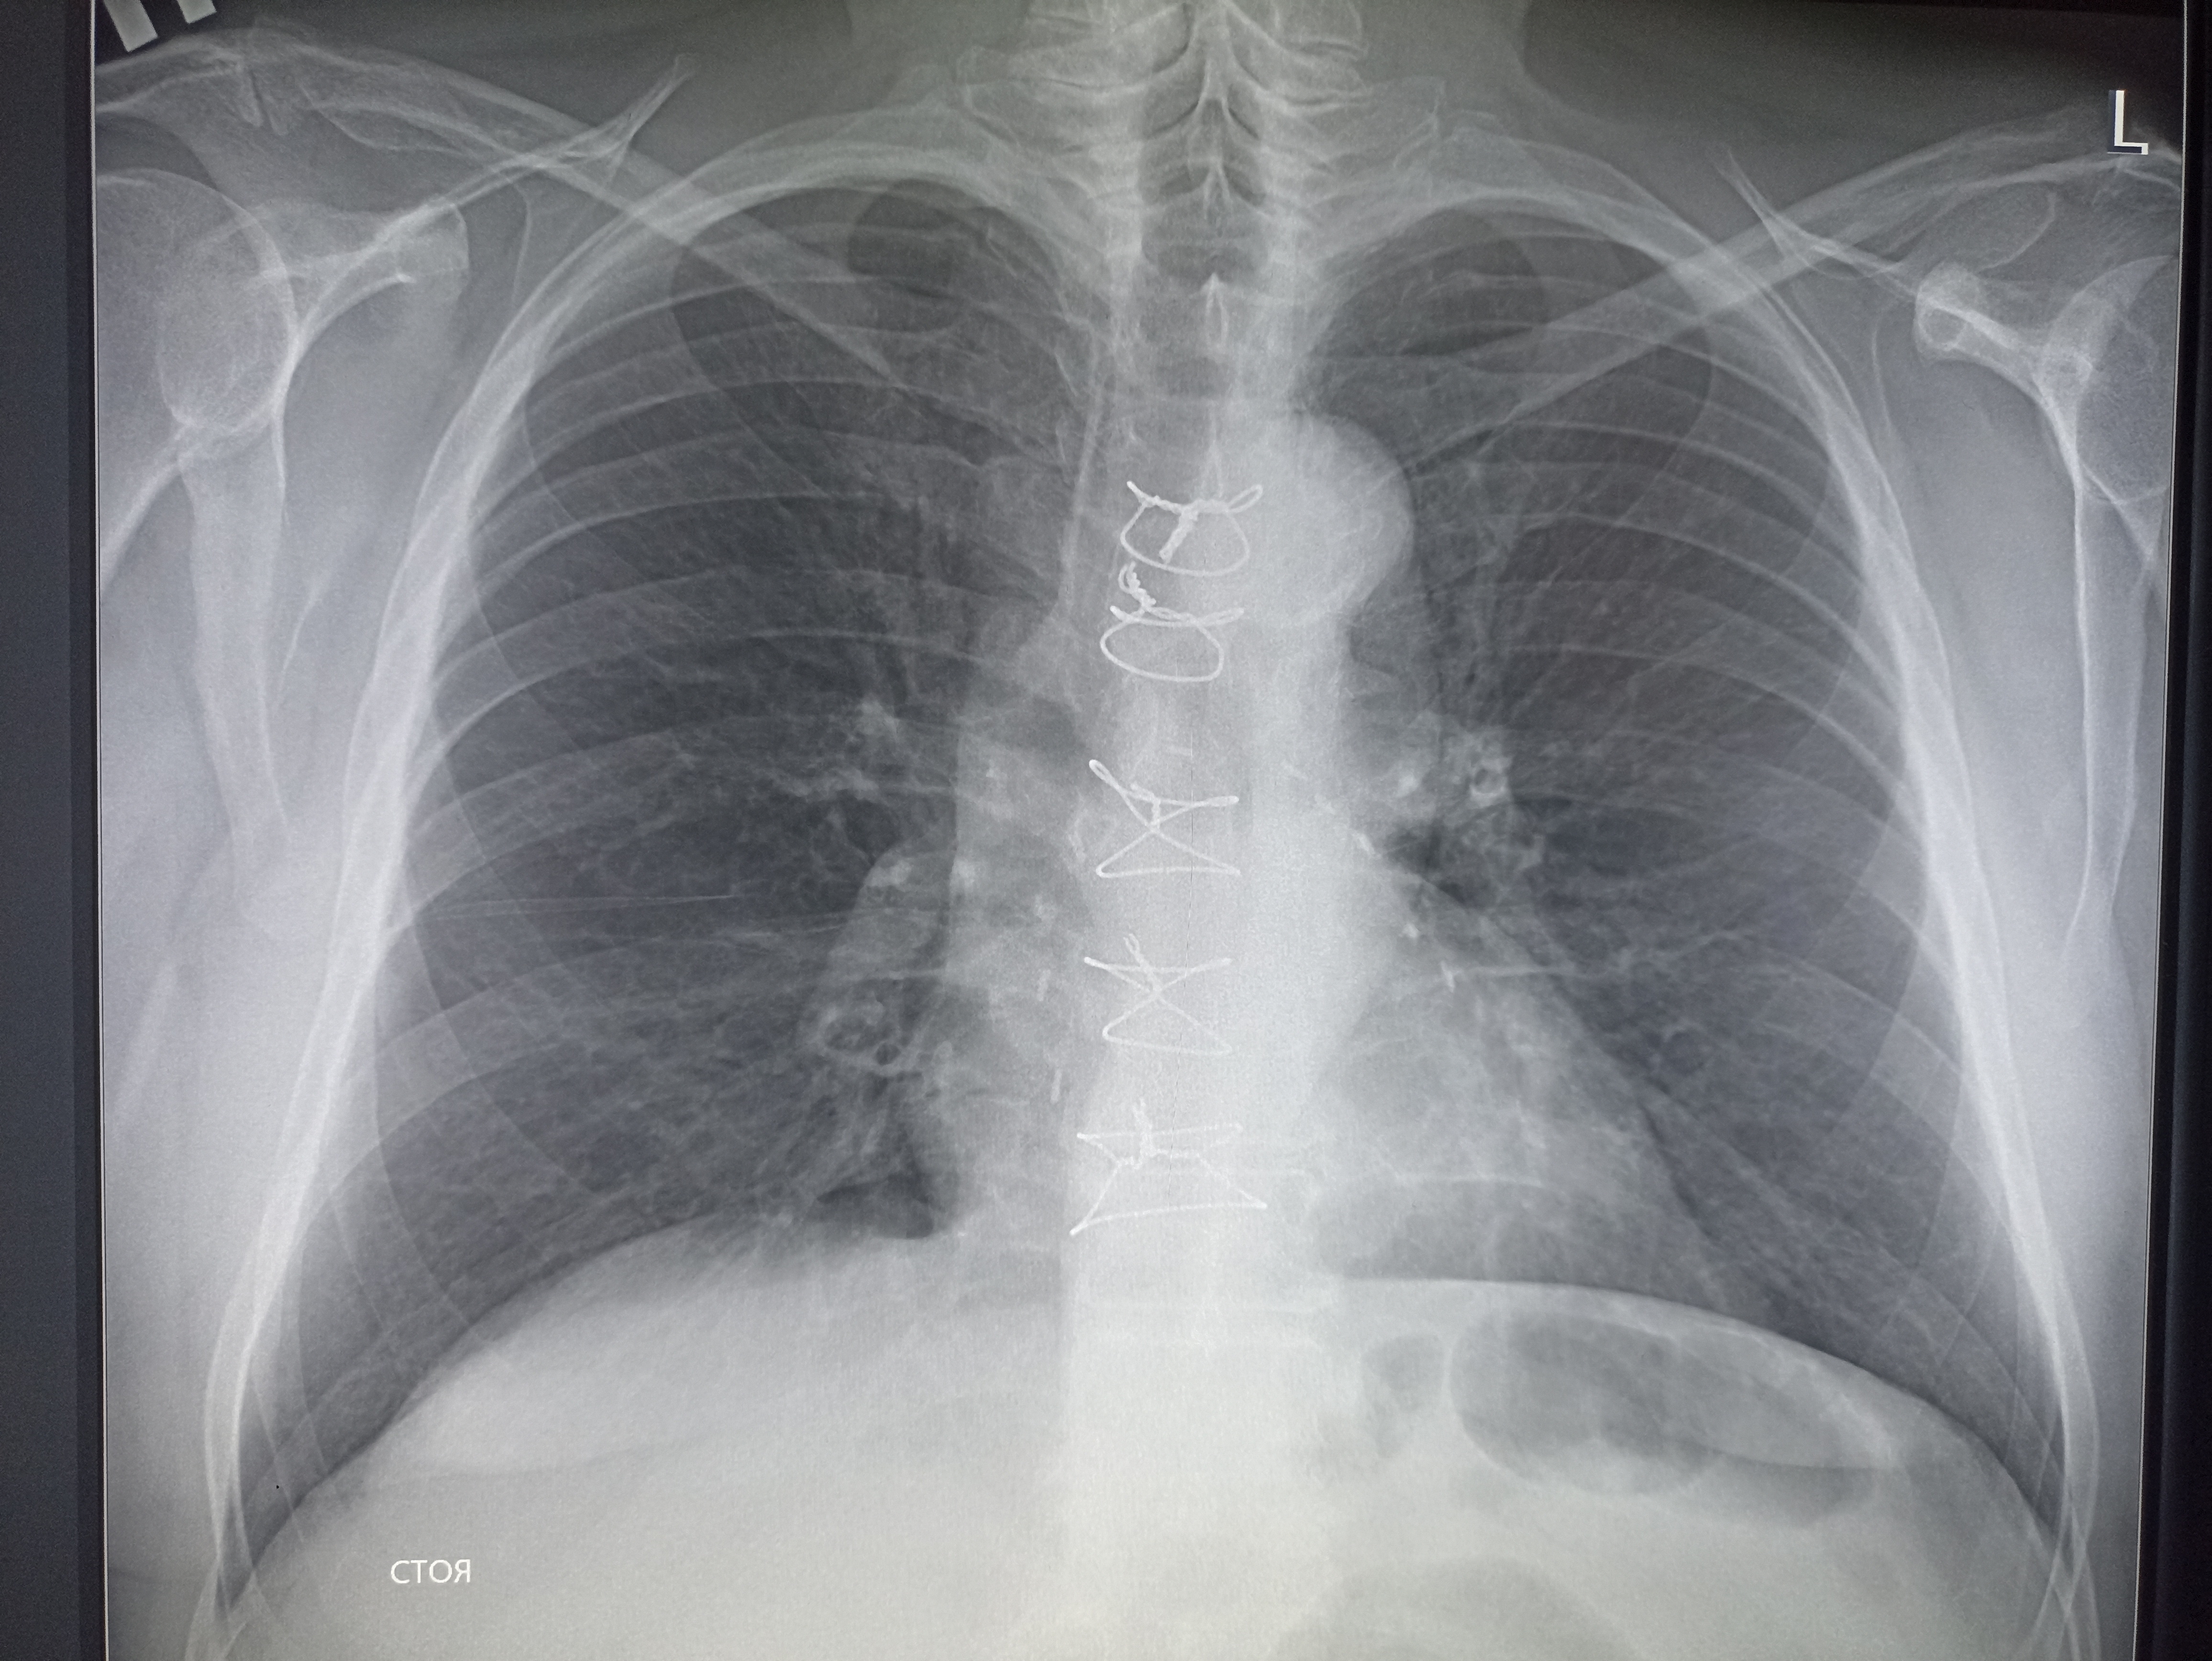

IMG20251009125406.jpg

Где пиздецома?

>>325599559

Типичный рак легких

>>325599617

Сфигаль?

>>325599891

тут явно что то справа. Там скобы после операции, туда отклоняется трахея (?) и средостение. Может часть легкого удалили?

тут затемнения двухсторонние. Почему бы не пневмония?

>>325600460

Переломы ребер не смущают? Ну и там траьею толкает скорее всего расширеная аорта и камеры сердца.

вообще, как клинический диагноз. я бы предположил тубик, тут и затемнения есть и в корнях кругленькие л/у? и какая то диссеминация справа.

>>325598833

тут справа что- то удаляли, все средостение смещено.